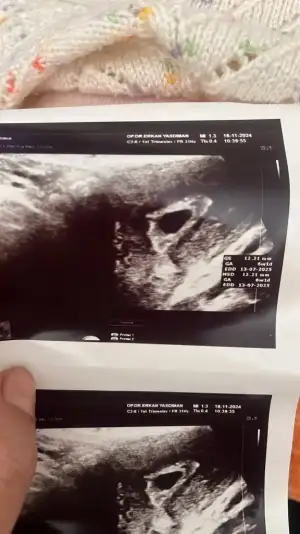

Canım yeni geldim doktordan karından bebegi ve kalp atışını gördük kanamam hala var biraz çogaldı 5 tane igne yazdı yolk kesesi felan oluşmuş ama bebek minnacık daha ilk attıgım ilk gittigim vajinal digeri karından karından bebek görüldü

Eklentiler

• IMG_1518.webp

IMG_1518.webp

24,3 KB · Görüntüleme: 39